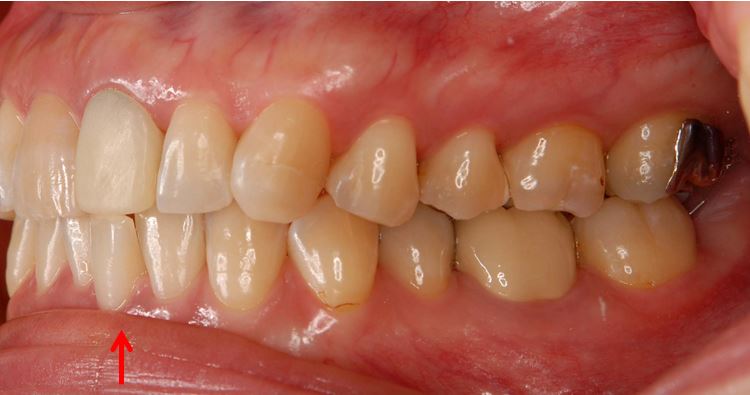

また、この症例では、矯正治療の恩恵がもうひとつありました。下の写真をご覧ください。

治療前: デコボコの歯がぶつかってしまい、上の前歯(差し歯)の高さが周りの歯と合っていない。例え1mmの高さの違いでも目立ってしまう事があります・・・

治療後: 下の前歯のデコボコが解消し、周りと調和の取れた差し歯を入れることができました!

上の前歯を治す時に、下の前歯を矯正すると、上の前歯の差し歯のクオリティーが飛躍的に向上することがあります。

但し、全体のバランスをみて「部分矯正」が適応できるか判断する必要があります。安易に行うと、歯は綺麗に並んだが、上下の前歯の間に前後的に大きな隙間ができた(過度なオーバージェット)やかみあわせが深くなる(ディープバイト)等の予期せぬ状態が生じることがあります。正確な診査・診断が矯正治療には常に求められます。